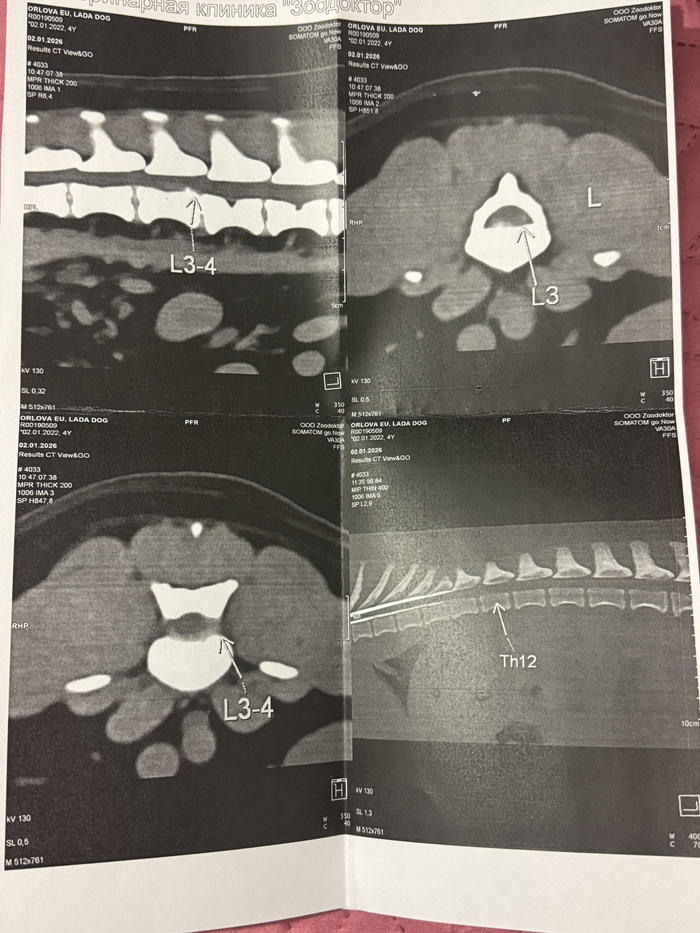

2 января ездили на КТ , где , к сожалению, диагноз подтвердился. У Ладочки 4 степень глубокой болевой чувствительности. Это критическое состояние для экстренного вмешательства специалистов.